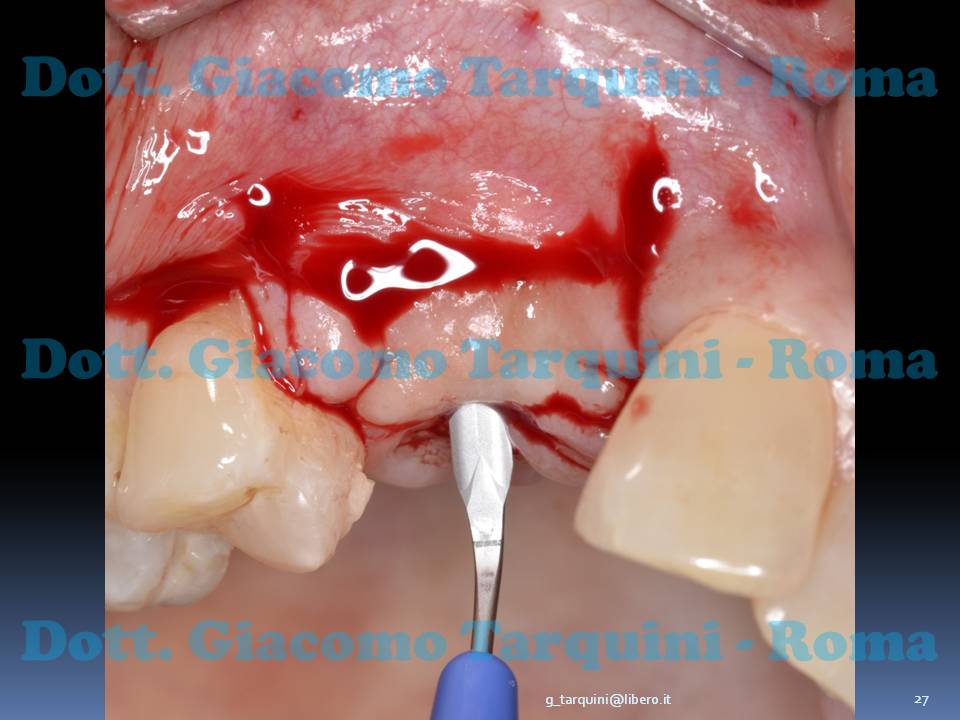

Si esegue una procedura di lembo palatino assottigliato

post-729-0-41842600-1489584808_thumb.jpg

post-729-0-91165100-1489584811_thumb.jpg

Si verifica il grado di passivita' del lembo buccale

post-729-0-80755800-1489584815_thumb.jpg